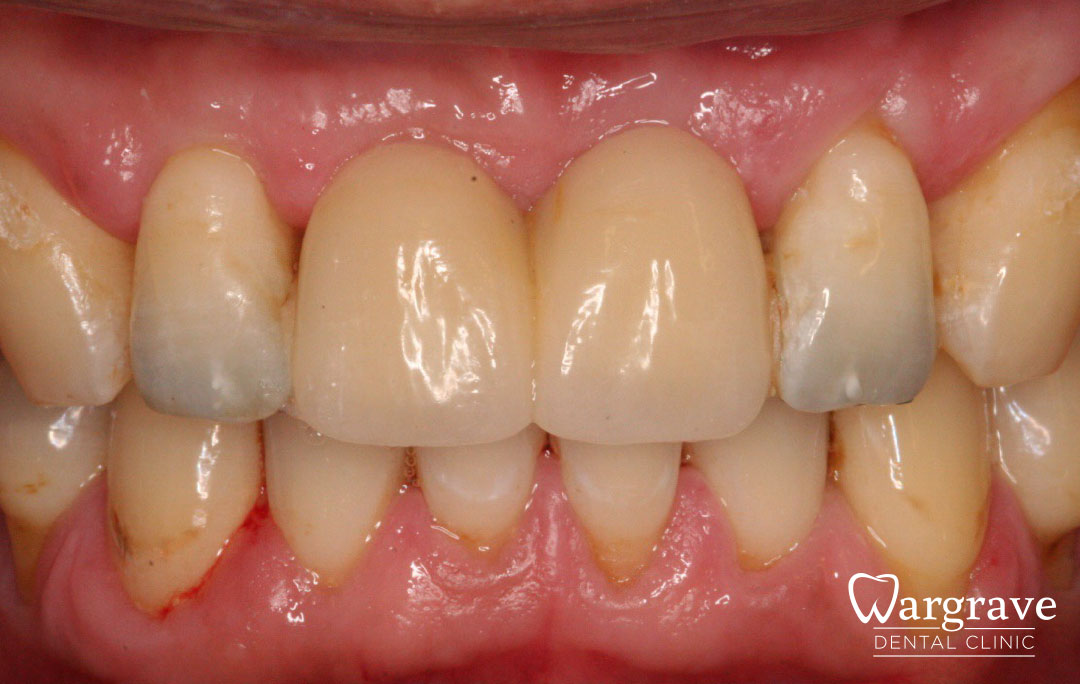

Healthy Smiles These are more advanced examples of different treatments available.All cases shown were carried out by Dr R Khurana unless otherwise stated. Immediate implants Anterior Mandible Bone Regeneration Anterior Mandibular Implant Bridge Maxillary Anterior Implant Bridge Implant stabilised ‘Life Like’ replacement dentures Implant Bridge after 10-years with zero bone loss Implant examples including ZBLC concepts Adhesive Bridge solution for a missing premolar Multidisciplinary care Orthodontics, Replacement veneers and composite bonding Adhesive Bridge solution for missing central incisors Replacement crown, Veneer and Composite Bonding Replacement Crowns and Veneer Injection Moulding using Composite Resin Equilibration Tooth Whitening to treat Developmental Discolouration